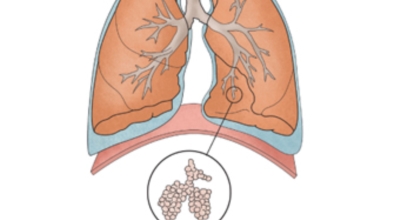

폐암 초기증상 - 호흡 곤란

폐암 환자의 1/4에서 나타나는 일반적인 증상으로 호흡곤란이 일어나는 이유는 다발성 폐전이가 폐 양쪽에서 발견되는 경우 생기게 될 수 있으며 폐암과 또한 악성 흉수가 동반되는 경우 발생해요. 일반적인 때와 다르게 숨이 차는 느낌이 들면서 숨을 들이쉬고 내쉴때 쌕쌕 거리는 소리나 나온다면 폐암 초기증상을 의심해 볼 수 있답니다.